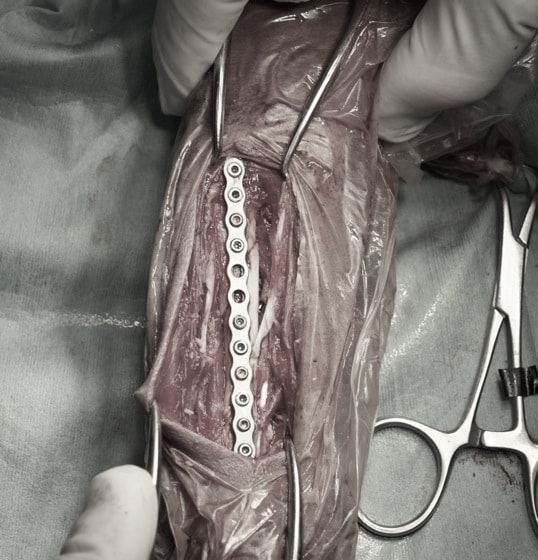

トイプードル 右遠位橈尺骨短斜骨折のALPSによる内固定

当院ではAdvanced Locking plate system(ALPS)と、Locking compression plate system(LCPS)という骨接合法で骨折症例の治療を行っています。

従来型のプレートのように広い面積で骨と接するプレートを用いて固定を行った場合、プレート下の骨はプレートとの接触面において血行が絶たれ壊死し、それがリモデリングされると骨密度が低下する。この骨密度の低下防ぐために、骨折部局所への血行を温存することの重要性が近年改めて認識されるようになってきている。Advaed Locking Plate System (ALPS)は従来型のプレートシステムの欠点を改良し、より使いやすく、より骨への血行を阻害しないようにというコンセプトで作られた。